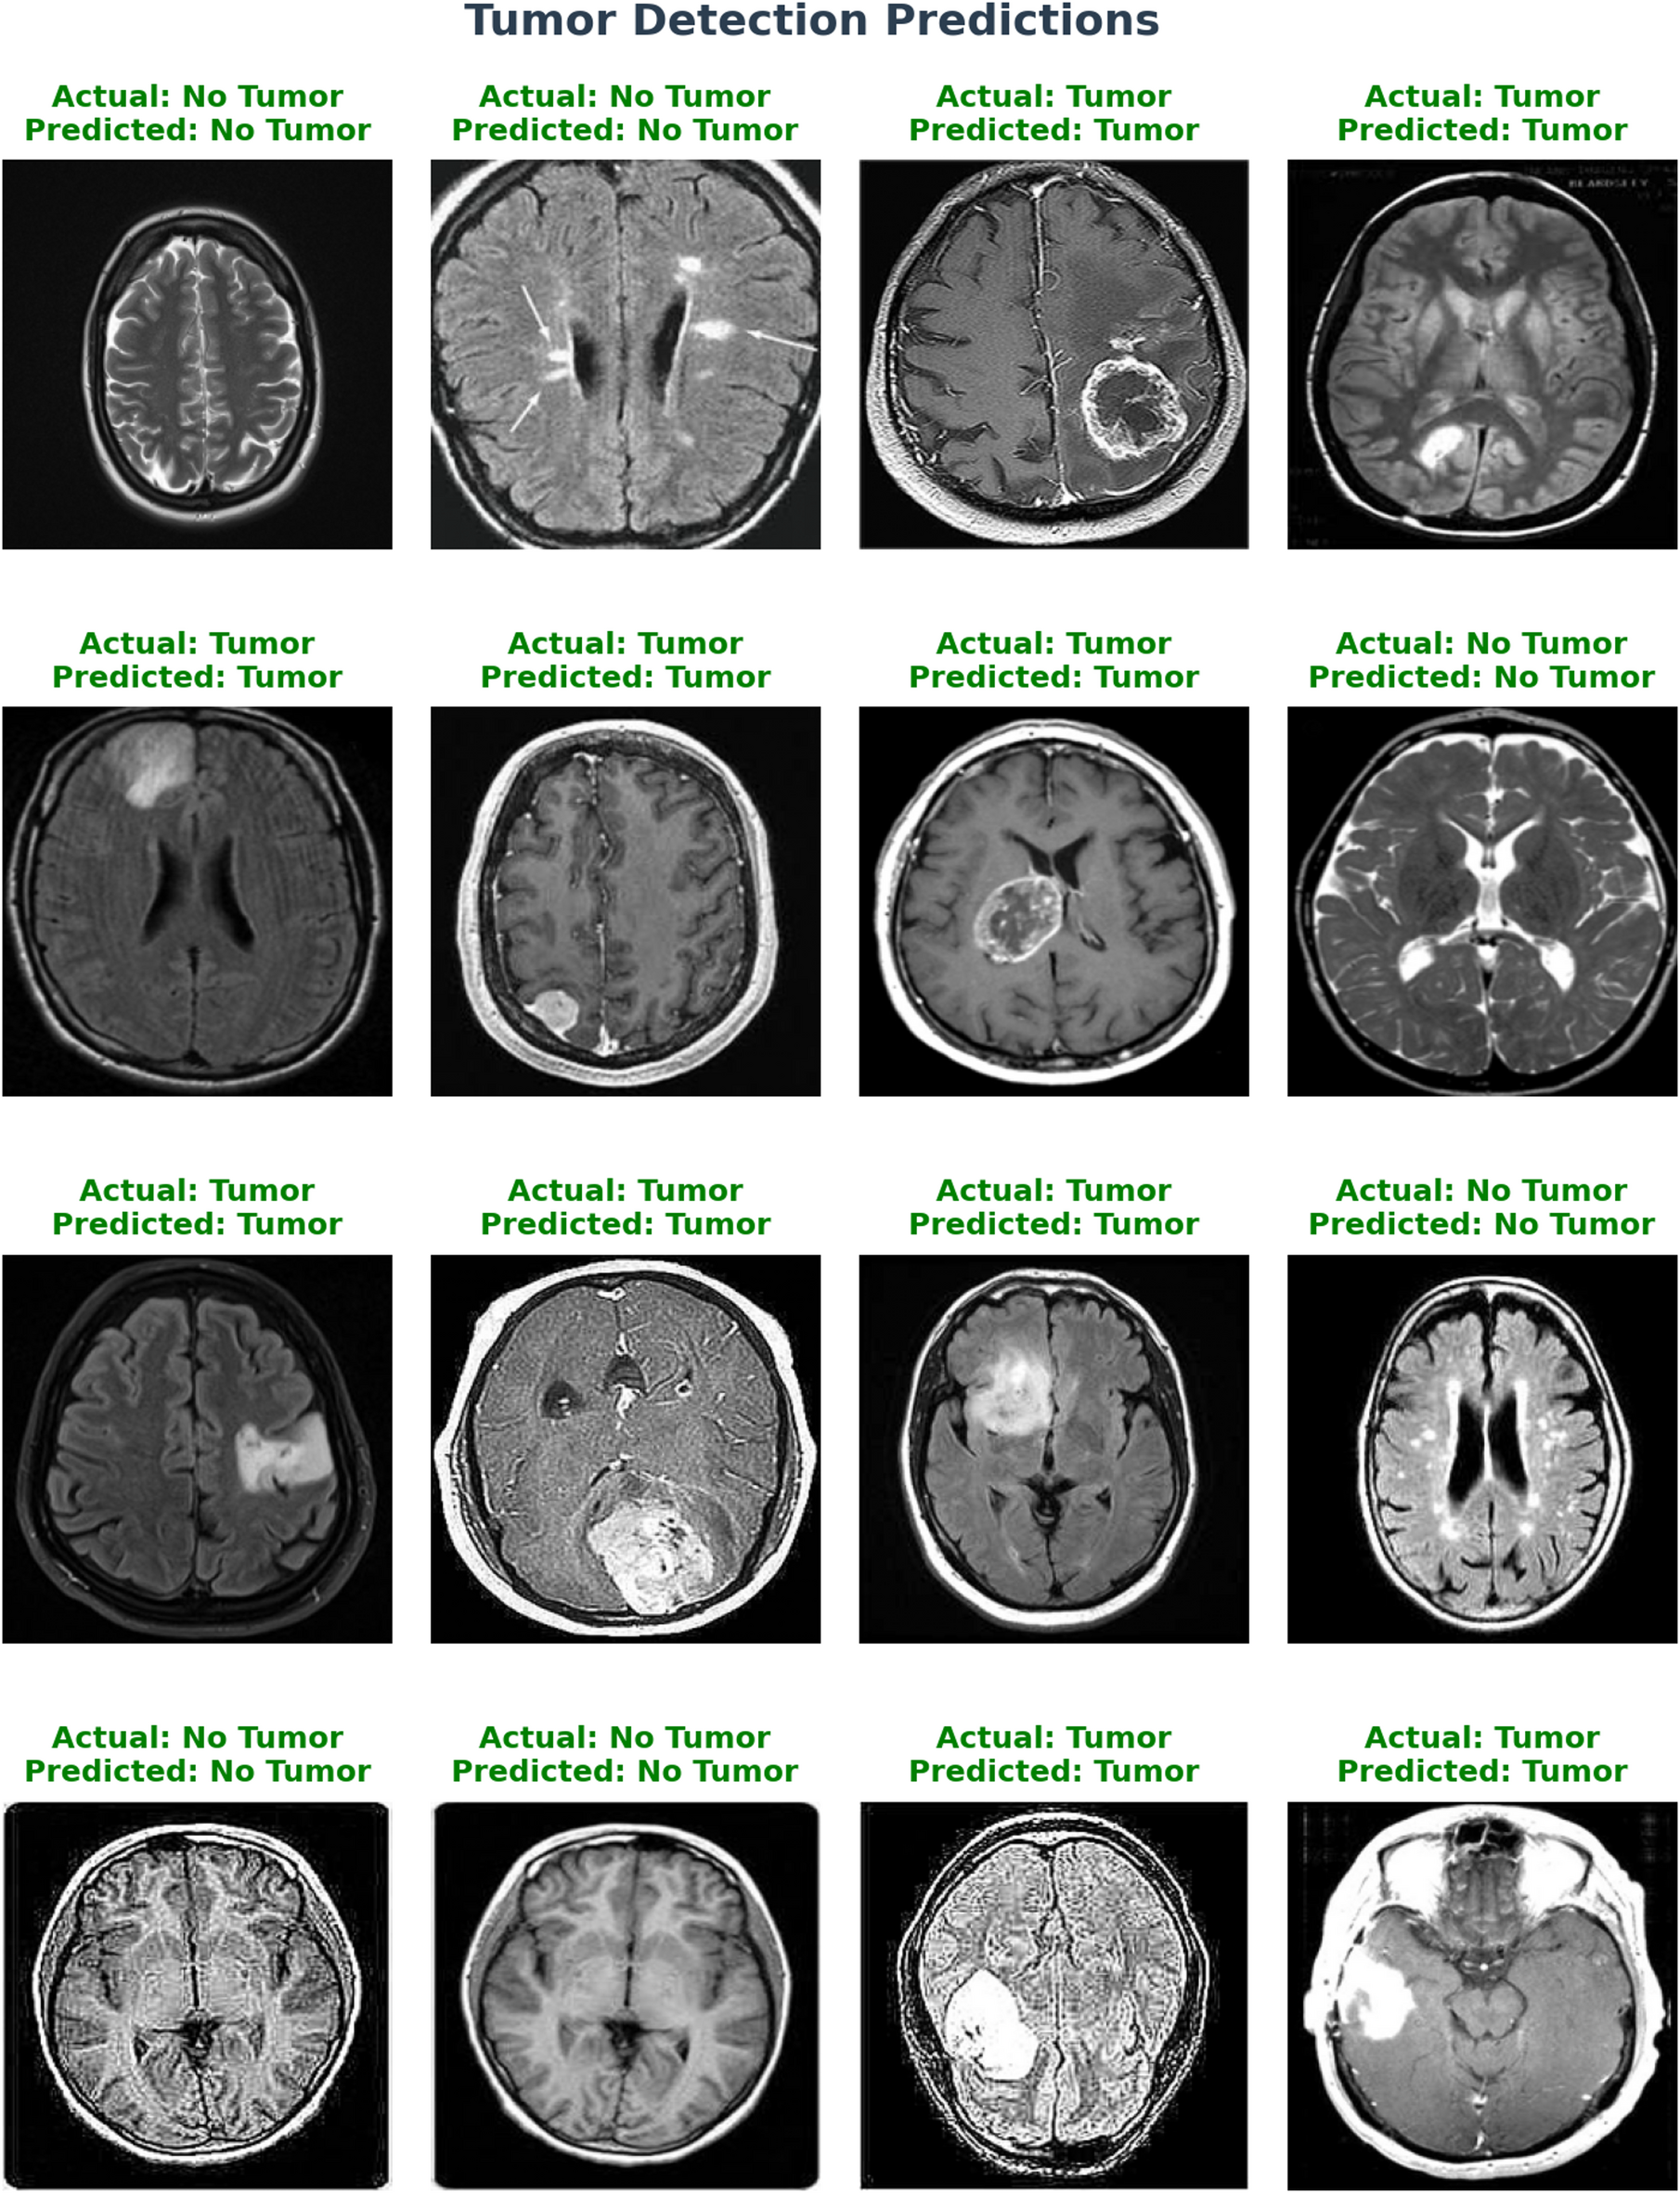

Fig. 10

Tumor detection prediction.